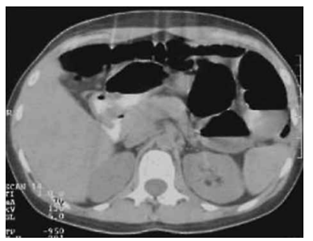

Paciente de 64 anos, portadora de diabetes mellitus tipo

2, hipertensão arterial, hiperuricemia e hipertrigliceridemia, é submetida a colectomia segmentar por neoplasia

de cólon há 5 dias. Evolui com febre persistente, dor

abdominal progressiva e inapetência na enfermaria. Nas

últimas 12 horas, apresentou vômitos biliosos e rebaixamento do nível de consciência sendo transferida para

unidade de terapia intensiva.

Ao exame físico: PA: 78 x 50 mmHg; FC: 124 bpm; FR: 28 irpm; SatO₂: 94% O₂ nasal; temperatura: 38,9 °C; pele fria; tempo de enchimento capilar 5 s; Glasgow: 13; abdome: distendido, doloroso difusamente, sinais de defesa involuntária e descompressão brusca dolorosa. Exames laboratoriais iniciais: lactato: 5,2 mmol/L; leucócitos: 24.000/mm³; plaquetas: 88.000/mm³; creatinina: 2,3 mg/dL (VR <1,2); bilirrubina total: 2,1 mg/dL.

Realizou a tomografia de abdome sem contraste a seguir:

(Arquivo pessoal; imagem usada com autorização)

Qual é a medida fundamental, associada à antibioticoterapia e ao suporte hemodinâmico, para o manejo desse caso?